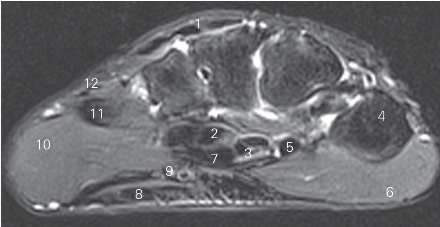

图4-46 经掌骨近侧四分之一的横断层MR T2WI FS

1 指伸肌 extensor digitorum 2 指深屈肌 flexor digitorum profundus

3 正中神经 median nerve 4 第一掌骨 1st metacarpal bone

5 拇长屈肌腱 tendon of flexor pollicis longus

6 大鱼际 thenar

7 指浅屈肌腱 tendon of flexor digitorum superficialis

8 掌腱膜 palmar aponeurosis 9 尺神经 ulnar nerve

10 小鱼际 hypothenar 11 第五掌骨 5th metacarpal bone

12 小指伸肌腱 tendon of extensor digiti minimi

图4-47 经掌骨中远四分之一的横断层MR T1加权图像

1 伸肌腱 tendon of extensor 2 骨间背侧肌 dorsal interossei

3 拇指近节指骨 proximal phalanx of thumb

4 拇收肌 adductor pollicis 5 拇长屈肌 flexor pollicis longus

6 指浅屈肌 flexor digitorum superficialis

7 指深屈肌 flexor digitorum profundus

8 小鱼际 hypothenar 9 第五掌骨5th metacarpal bone

10 骨间掌侧肌 palmar interossei